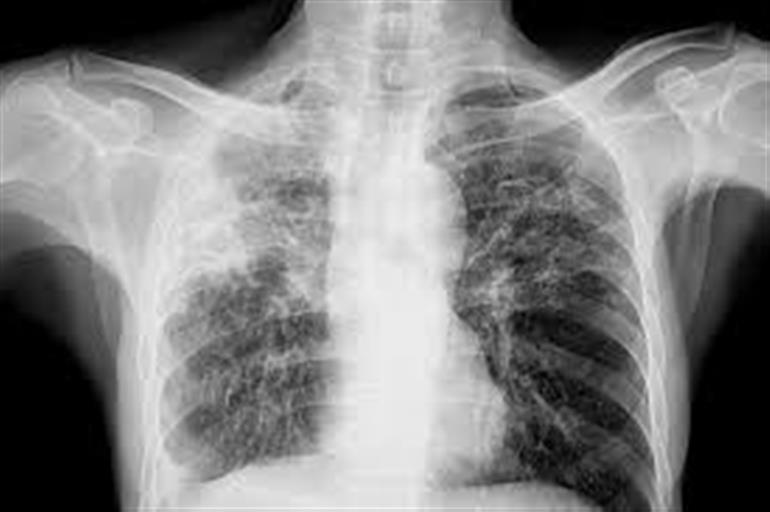

ਟੀ.ਬੀ. ਤੇ ਛਾਤੀ ਰੋਗਾਂ ਦੀ ਇੱਕ ਦਿਨਾਂ ਸੀ.ਐਮ.ਹੀ ਅੱਜ

ਪਟਿਆਲਾ :  ਸਰਕਾਰੀ ਮੈਡੀਕਲ ਕਾਲਜ ਦੇ ਛਾਤੀ ਤੇ ਸਾਹ ਦੇ ਰੋਗਾਂ ਦੇ ਵਿਭਾਗ ਤੇ ਟੀ.ਬੀ. ਹਸਪਤਾਲ ਵੱਲੋਂ 23 ਫ਼ਰਵਰੀ ਨੂੰ ਇੱਕ ਦਿਨੀਂ ਸੀ.ਐਮ.ਈ. (ਕੰਟਿਨਿਊਇੰਗ ਮੈਡੀਕਲ ਐਜੂਕੇਸ਼ਨ) ਪ੍ਰੋਗਰਾਮ ਕਰਵਾਇਆ ਜਾ ਰਿਹਾ ਹੈ। ਇਸ ਤੋਂ ਪਹਿਲਾਂ 22 ਫ਼ਰਵਰੀ ਨੂੰ ਨਾਨ-ਇੰਵੇਸਿਵ ਵੈਂਟੀਲੇਸ਼ਨ 'ਤੇ ਅੱਧੇ ਦਿਨ ਦਾ ਵਰਕਸ਼ਾਪ ਕਰਵਾਈ ਗਈ, ਜਿਸ ਦੀ ਅਗਵਾਈ ਡਾ. ਜੀ.ਸੀ. ਖਿਲਨਾਨੀ (ਸਾਬਕਾ ਮੁਖੀ, ਏਮਜ਼, ਨਵੀਂ ਦਿੱਲੀ) ਅਤੇ ਡਾ. ਏ.ਕੇ. ਮੰਡਲ (ਫੋਰਟਿਸ, ਮੋਹਾਲੀ) ਵੱਲੋਂ ਕੀਤੀ ਗਈ।

ਜ਼ਿਕਰਯੋਗ ਹੈ ਕਿ ਇਹ ਲਗਾਤਾਰ ਚੌਥੀ ਸਾਲ ਇਹ ਪ੍ਰੋਗਰਾਮ ਕਰਵਾਇਆ ਜਾ ਰਿਹਾ ਹੈ, ਇਸ ਸਾਲ ਦਾ ਵਿਸ਼ਾ ‘ਛਾਤੀ ਤੇ ਸਾਹ ਦੇ ਰੋਗਾਂ ਦੇ ਇਲਾਜ ’ਚ ਹੋਈਆਂ ਤਰੱਕੀਆਂ’ ਹੈ। ਏਮਜ਼ ਨਵੀਂ ਦਿੱਲੀ, ਪੀ.ਜੀ.ਆਈ ਚੰਡੀਗੜ੍ਹ, ਜੀ.ਐਮ.ਸੀ.ਐੱਚ ਚੰਡੀਗੜ੍ਹ, ਨਵੀਂ ਦਿੱਲੀ ਟੀ.ਬੀ. ਸੈਂਟਰ, ਮੈਟਰੋ ਰੈਸਪਿਰੇਟਰੀ ਸੈਂਟਰ ਨੋਇਡਾ, ਅਤੇ ਫੋਰਟਿਸ ਮੋਹਾਲੀ ਦੇ ਮਾਹਿਰ ਫੈਕਲਟੀ ਮੈਂਬਰ ਆਪਣੇ ਗਿਆਨ ਅਤੇ ਅਨੁਭਵ ਨੂੰ ਸਾਂਝਾ ਕਰਨ ਲਈ ਇਕੱਠੇ ਹੋ ਰਹੇ ਹਨ।

ਸੀ.ਐਮ.ਈ ਵਿੱਚ ਐਂਟੀਬਾਇਓਟਿਕਸ ਦੀ ਸਮਝਦਾਰੀ ਨਾਲ ਵਰਤੋਂ ਬਾਰੇ ਚਰਚਾ ਕੀਤੀ ਜਾਵੇਗੀ, ਜਿਸ ਵਿੱਚ ਡਾ. ਜੀ.ਸੀ. ਖਿਲਨਾਨੀ, ਡਾ. ਐੱਸ.ਕੇ. ਜਿੰਦਲ, ਡਾ. ਆਸ਼ੂਤੋਸ਼ ਐਨ. ਅਗਰਵਾਲ ਅਤੇ ਡਾ. ਦੀਪਕ ਅਗਰਵਾਲ ਦੀ ਟੀਮ ਆਪਣੀ ਰਾਏ ਪੇਸ਼ ਕਰੇਗੀ। ਇਨ੍ਹਾਂ ਵਿਦਵਾਨਾਂ ਵੱਲੋਂ ਕ੍ਰੋਨਿਕ ਓਬਸਟ੍ਰਕਟਿਵ ਪਲਮਨਰੀ ਡਿਜ਼ੀਜ਼ (ਸੀ.ਓ.ਪੀ.ਡੀ) ਤੇ ਵੀ ਵਿਸ਼ਲੇਸ਼ਣਾਤਮਿਕ ਚਰਚਾ ਹੋਵੇਗੀ, ਜੋ ਧੂਮਰਪਾਨ ਨਾਲ ਜੁੜੀ ਇੱਕ ਗੰਭੀਰ ਬਿਮਾਰੀ ਹੈ। ਸਮੋਕਿੰਗ ਛੱਡਣ ਦੇ ਢੰਗ ਅਤੇ ਇਸਦੇ ਉਪਚਾਰਕ ਪੱਖਾਂ ਤੇ ਵੀ ਵਿਚਾਰ-ਵਟਾਂਦਰਾ ਕੀਤਾ ਜਾਵੇਗਾ।

ਡਾ. ਦੀਪਕ ਤਲਵਾਰ ਅਸਥਮਾ ਦੇ ਉਹਨਾਂ ਮਰੀਜ਼ਾਂ ਲਈ ਨਵੀਂਆਂ ਥੈਰੇਪੀ ਵਿਕਲਪਾਂ 'ਤੇ ਚਾਨਣਾ ਪਾਉਣਗੇ, ਜਿਨ੍ਹਾਂ ਦਾ ਰੋਗ ਪੂਰੀ ਤਰ੍ਹਾਂ ਨਿਯੰਤਰਨ ਵਿੱਚ ਨਹੀਂ ਆਉਂਦਾ। ਡਾ. ਕੇ.ਕੇ. ਚੋਪੜਾ ਅਤੇ ਡਾ. ਅਸ਼ਵਨੀ ਖੰਨਾ ਨੈਸ਼ਨਲ ਟਿਊਬਰਸਕਲੋਸਿਸ ਇਲੀਮੀਨੇਸ਼ਨ ਪ੍ਰੋਗਰਾਮ ਹੇਠ ਟੀ.ਬੀ. ਦੇ ਨਵੇਂ ਇਲਾਜ ਰੈਜੀਮੈਨ ਬਾਰੇ ਜਾਣਕਾਰੀ ਦੇਣਗੇ। ਇਸਦੇ ਇਲਾਵਾ, ਰੈਸਪਿਰੇਟਰੀ ਬਿਮਾਰੀਆਂ ਵਿੱਚ ਟੀਕਾਕਰਨ ਦੀ ਭੂਮਿਕਾ, ਸਲੀਪ ਡਿਸਆਰਡਰਡ ਬ੍ਰਿਥਿੰਗ ਅਤੇ ਡਿਫਿਊਜ਼ ਪੈਰੇਨਕਾਈਮਲ ਲੰਗ ਡਿਜ਼ੀਜ਼ ਜੈਸੇ ਵਿਸ਼ਿਆਂ 'ਤੇ ਵੀ ਚਰਚਾ ਹੋਣ ਦੀ ਉਮੀਦ ਹੈ।

ਇਸ ਸਮਾਰੋਹ ਵਿੱਚ ਪੰਜਾਬ ਅਤੇ ਨੇੜਲੇ ਰਾਜਾਂ ਤੋਂ ਲਗਭਗ 150 ਡੈਲੀਗੇਟਸ ਦੀ ਸ਼ਮੂਲੀਅਤ ਹੋਵੇਗੀ। ਸੀ.ਐਮ.ਈ. ਡਾਕਟਰਾਂ ਅਤੇ ਮੈਡੀਕਲ ਵਿਦਵਾਨਾਂ ਲਈ ਇੱਕ ਮਹੱਤਵਪੂਰਨ ਵਿਦਿਅਕ ਅਤੇ ਆਚਰਚਾਤਮਕ ਮੰਚ ਸਾਬਤ ਹੋਵੇਗਾ, ਜਿਸ ਦੌਰਾਨ ਉਨ੍ਹਾਂ ਨੂੰ ਪਲਮਨਰੀ ਮੈਡੀਸਨ ਦੇ ਨਵੇਂ ਵਿਕਾਸ ਅਤੇ ਉਪਚਾਰਕ ਪੈਰਾਮਿਟਰਾਂ ਬਾਰੇ ਜਾਣਨ ਦਾ ਮੌਕਾ ਮਿਲੇਗਾ।